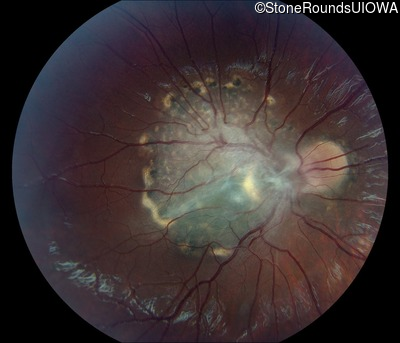

This 9 year old male was noted to have some crossing of his eyes at 2 months of age and the eye exam which followed identified a retinal lesion in the right eye. When he was six years old an epiretinal membrane was noted in his left eye. Two years later it was decided that it was a thin hamartoma in that eye as well. He underwent neuroimaging at age 7 which identified bilateral acoustic neuromas.